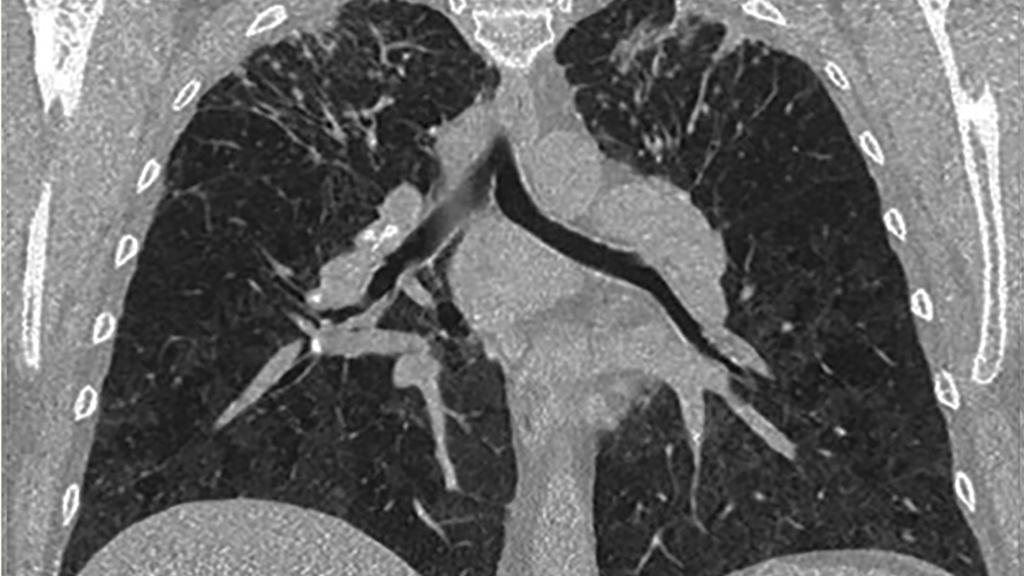

A high-resolution CT lung scan displaying scarring typical of beryllium-induced disease

An X-ray at this time was negative for lesions or opacifications. A high-resolution CT in 2005, however, revealed confluent apical infiltrates in both lungs and evidence of mid-zone granularity. As a result, Mr. W’s pulmonologist diagnosed pulmonary sarcoidosis and referred him to the Harron Lung Center for treatment.